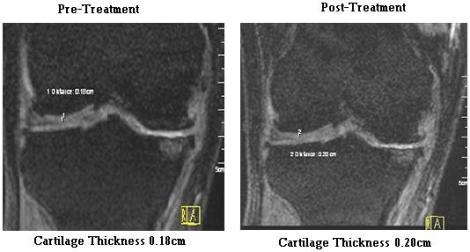

* This is for assessment by a radiologist